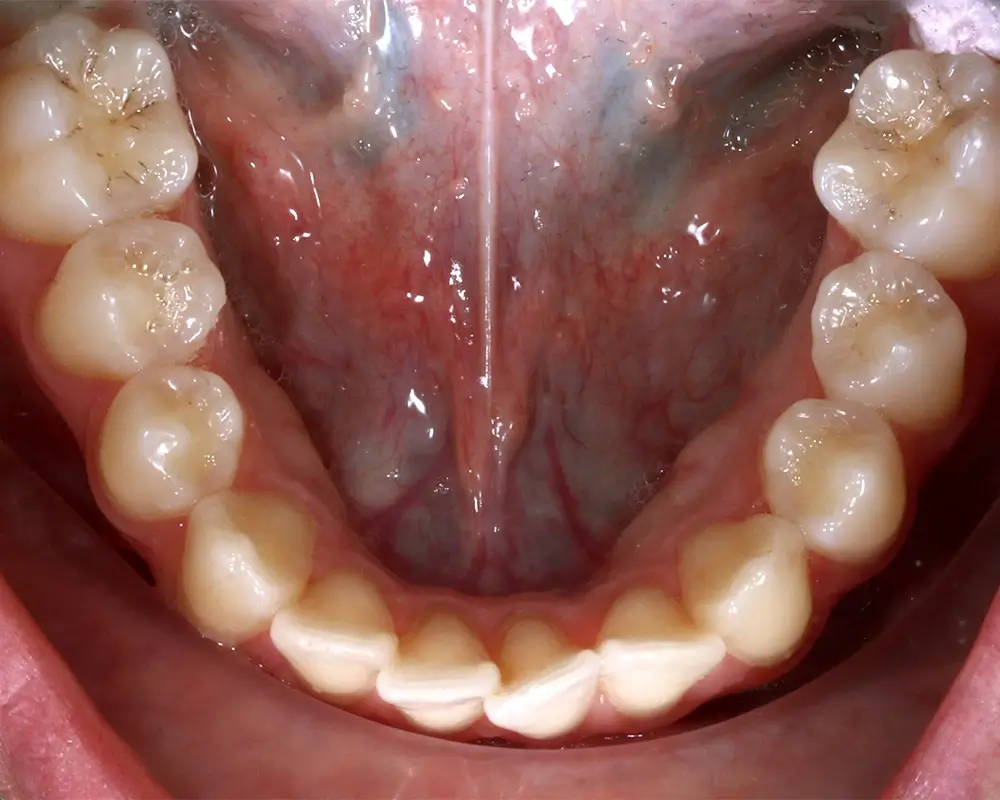

Открытый прикус - Кейс 6

Эффективность устранения дефекта прикуса посредством элайнеров FlexiLigner.

Количество кап НЧ

Количество кап ВЧ